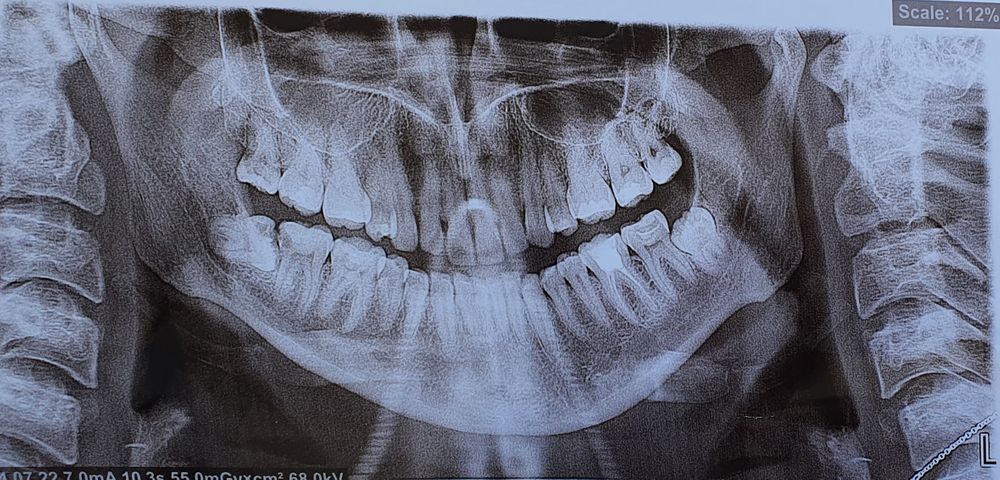

У вас кариес на 7 зубе (с задней поверхности) нижней челюсти справа из-за лежащего 8 зуба, а вы все ещё в раздумьях🤦🏼‍♀️🤦🏼‍♀️🤦🏼‍♀️🤦🏼‍♀️🤦🏼‍♀️Слушайте своего доктора, в первую очередь Изображение

Правая убила вам семерку. Не запускайте тему удаления и тему лечения 7, нелеченый пульпит = периодонтит, а это потеря зуба.

Оба удалять, один растёт поперёк, другой в зуб прямо упирается

Правую прям обязательно как можно скорее. Судя по пятнам, на ней и соседнем 7 зубе зубе кариес и недалеко до пульпита. Левая менее критична, но желательно тоже удалить.

Обязательно удалить, они сдвигают зубы. Даже по снимку видно. Это не больно, просто неприятно. Главное найти хорошего хирурга-стоматолога, для них это обычное дело. Вначале один, потом второй) тот что справа вообще фигня))

Так как семерки упираются в восьмерки, между ними нет кости, то такие надо удалять из-за опасности потерять семерки. В прошлом году через раз мне говорили, что надо и не надо. А сейчас та терапевт, которая лечила, и которой вроде как пофиг было, сказала внезапно(рассмотрела ещё дополнительный Снимок), что надо. Блин, мне в прошлом году это сказал нормальный ортодонт. Хирург один тоже за, одному пофиг было. И так как мнения разделились, я не удаляла. А прошлым летом внезапно десна отодвинулась ( в моем то возрасте) и сделался карман! А этим летом внезапно «все же надо удалять» и вроде бы из-за этого кармана появилась боль. Короче, пора-пора делать дела. - Там , где у вас лежачий зуб, там более опасно место из-за кармана. Этот, наверное, лучше удалять первым. Слева тоже сильно в семерку прет. Я думаю, такой тоже надо удалять. Слишком близко. (Апдейт. Перечитала комментарии и рассмотрела снимок. Точно. Проблема уже настала и именно из-за этого кармана! Именно так она и выглядит. Лечить семерку и удалять восьмёрку все равно.) Они у вас не вылезут уже. Оба под костью, да ещё один лежачий. Который прямо, он упирается в 7 и в кость. Точно не вылезет. Только гипотетически проблему создаёт.